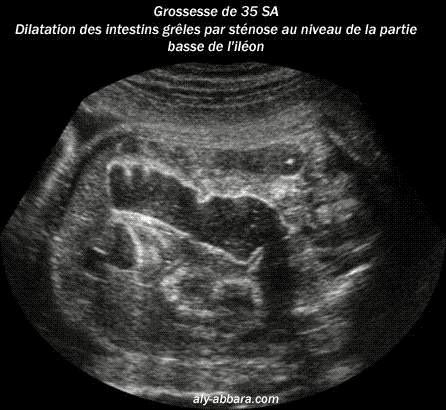

Grossesse de 35 semaines

d'aménorrhée avec la mise en évidence d'une dilatation

des anses grêles terminales

Il s'agit d'une sténose

basse, au niveau de la partie terminale de l'iléon. Caryotype

normal.